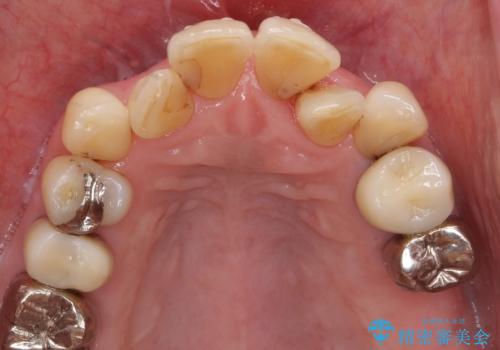

奥歯の違和感 再根管治療 40代女性

精査したところ、左上の大臼歯2本(左上67)が欠損しており、左上の小臼歯2本(左上45)は根が短く動揺があり根尖病変を認めました。

相談を重ねた上で小臼歯2本の再根管治療と連結補綴を行いました。

- ¥506,000 (再根管治療×2本、土台×2本、仮歯×2本、クラウン×2本) ※税込費用は治療当時の料金となります

クラウンの種類:オールセラミッククラウン スタンダード